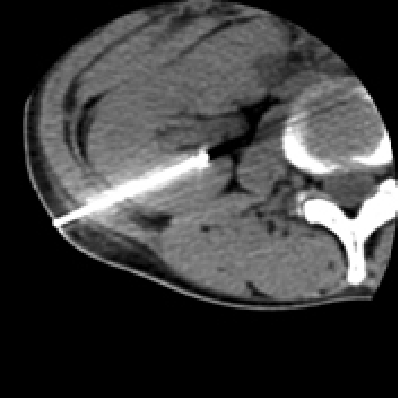

腎がんが多発するフォンヒッペルリンドウ病の患者様で、左腎はすでに他院で摘出されており、右腎しかない単腎の症例。ラジオ波治療後に腫瘍は完全に死滅している。この患者様はこの後、もう一つ別にあった腎がんも同様に治療された。このようにラジオ波治療は腎機能を低下させず、繰り返して治療できることから、このような単腎の多発腎がんでも治療が可能である。